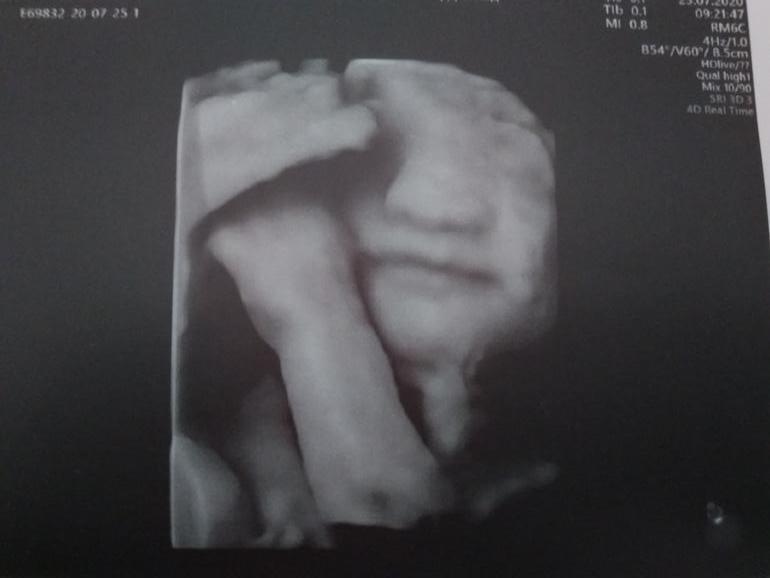

Из приятного. Сходили с мужем на 3д-узи. Малыш здоров, но процедуру традиционно проспал :) Сын немного дал себя рассмотреть, но фотогеничность - это не про него :)

А потом он засунул в рот палец и для верности закрылся ногой :) Разбудить его не смогли. Шоколадка не подействовала, переворачивание с боку на бок тоже и даже тычки датчиком оказались бесполезны. (Вот бы и после рождения он так крепко спал 😁)